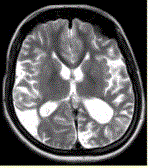

问题 女性,22岁。癫痫发作及智力异常。MRI显示见下图。 有关该病的描述正确的是(提示MRA所示如图。)

选项 A.双侧颈内动脉及其分支部分闭塞 B.双侧大脑后动脉狭窄、部分闭塞 C.颅底可见大量侧支循环形成 D.血管未见明显异常 E.双侧椎动脉显示清晰 F.双侧颈内动脉显示清晰

答案 ABC